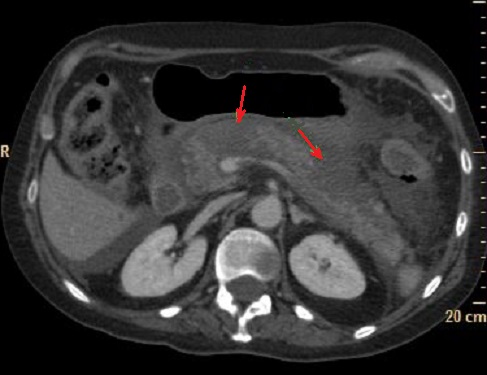

Image d'une pancreatite aigue

avec des foyers de absence de rehaussement a

hypodense apres de injection contrast intraveineuse

( fleche rouge ) . Image radiologique TDM phase

arteriel |

Aspect de reactionnel des

ganglions peri- pancreatique ( fleche rouge ) |